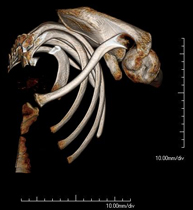

Exploració radiològica que mitjançant un sistema de raigs X i detectors que giren al voltant del pacient i que reconstrueixen les imatges per ordinador, permet l'estudi detallat de les clavícules. - TC Parrilla costal

Exploració radiològica que mitjançant un sistema de raigs X i detectors que giren al voltant del pacient i que reconstrueixen les imatges per ordinador, permet l'estudi detallat detalla de la Parrilla. - Angio- TC Cardíac o TC Cardíac